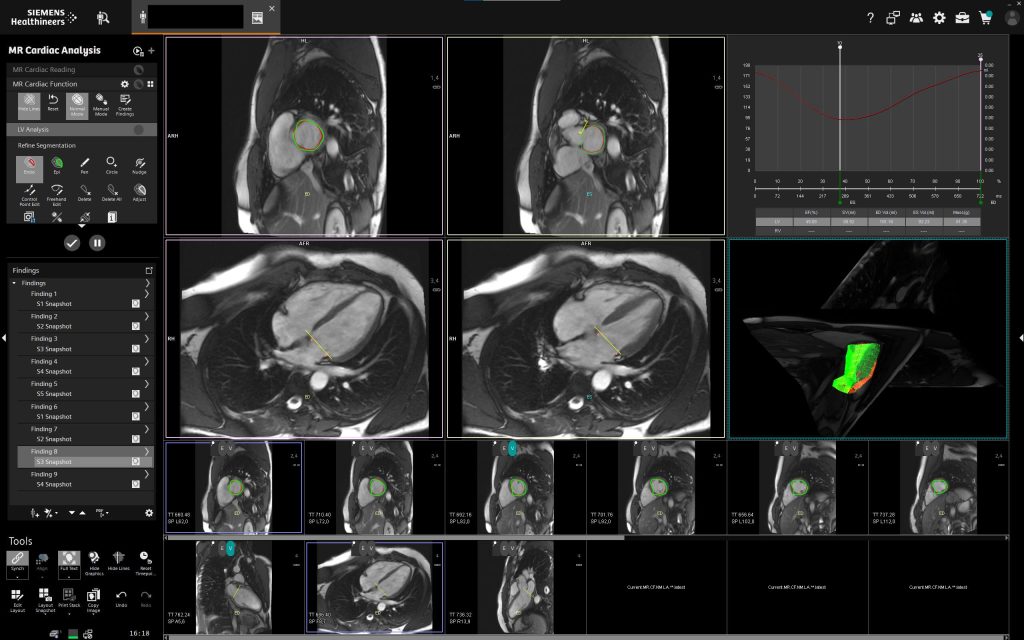

У клініці «Церебрум» МРТ серця представляє собою передовий неінвазивний метод, що дозволяє отримати надзвичайно точні дані про анатомію та функціональний стан серця.

Використання потужного магніту Siemens QS (45/200) із 16 канальною спеціалізованою серцевою котушкою та подальшою постобробкою на робочій станції Siemens Via забезпечує найвищий рівень діагностичної точності, недосяжний для традиційних методів дослідження.

- Комплексна функціональна оцінка — одночасний аналіз руху стінок серця, скоротливості шлуночків, роботи клапанів і кровотоку забезпечує всебічну оцінку роботи серцево-судинної системи.

- Сучасні технології обробки зображень та оперативне отримання результатів — високоякісні 3D-знімки та швидке формування детального висновку забезпечують прийняття точних клінічних рішень у найкоротші терміни.